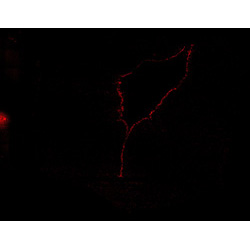

An anatomical analysis of the developing human midbrain from 6 post-conceptional weeks (PCW) to 22 PCW reveals increased tissue complexity, characterized by the emergence of dopaminergic nuclei, as highlighted by immunofluorescence analysis for tyrosine hydroxylase (TH).

TH

7PCW human midbrain

11PCW human midbrain